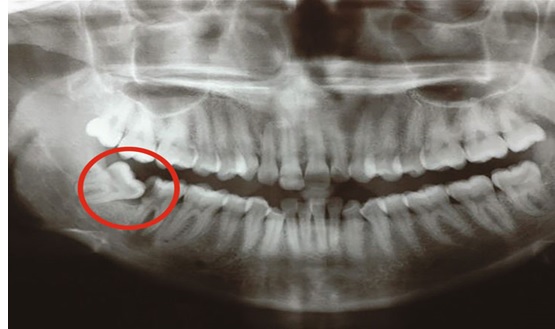

Sâu răng và tổn thương răng số 7: Do vị trí răng khôn nằm sâu trong cung hàm, việc vệ sinh thường gặp nhiều khó khăn. Khi răng khôn mọc lệch về phía trước, chúng có thể tạo khe hở với răng số 7, khiến thức ăn dễ mắc lại và khó làm sạch. Lâu ngày, vi khuẩn phát triển trong vùng này có thể gây sâu răng khôn, sâu răng số 7 hoặc viêm tủy răng, làm ảnh hưởng đến chức năng ăn nhai và có thể phải điều trị phức tạp hơn.

.jpg)

Hình ảnh răng khôn mọc lệch gây sâu răng số 7